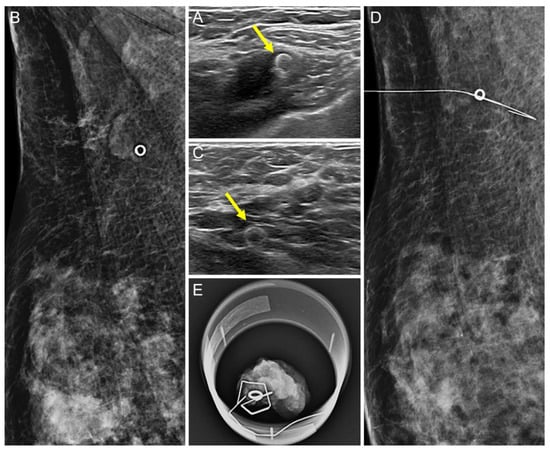

Comparison of the Ultrasound Visibility of Tissue Markers in Metastatic Lymph Nodes after Neoadjuvant Chemotherapy in Patients with Breast Cancer

3.1. Comparison of the US Visibility between the Two Tissue Markers after NAC